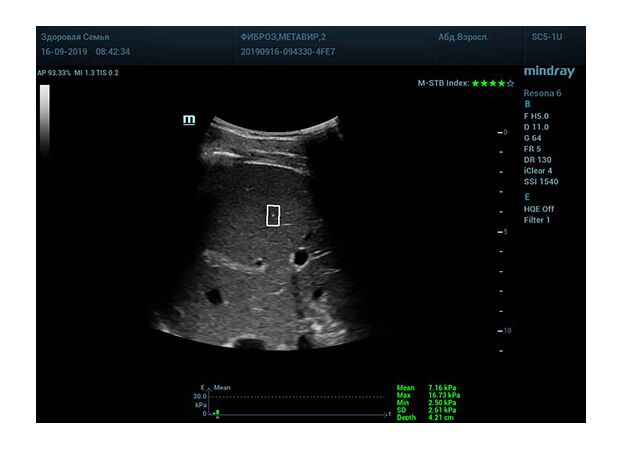

Определение плотности печени. Не ошибся ли оператор при измерении эластических свойств печени? Для оценки критериев качества предусмотрен индекс MBT, который покажет насколько «твердой» была рука оператора и двигалась ли печень. При MBT 5* рука тверда и показатели достоверны. Для оценки качества результатов используется IQR индекс, отображающий колебания показателей в точке измерения при расчете медианы. Показатели при IQR <30% считаются приемлемыми. Техника сканирования через межреберные промежутки требует размещение окна интереса на несколько сантиметром ниже капсулы, для исключения эффекта реверберации. Установка ROI на паренхиму без захвата сосудов, для исключения погрешностей измерения.

Стадия фиброза определяется по системе METAVIR Staging, построенной на данных биопсии и сопоставлении с данными эластографии. Своевременная диагностика фиброза, и начало его лечения, залог благоприятного исхода заболевания.

• METAVIRF2 – Портальный фиброз с вовлечением нескольких перегородок